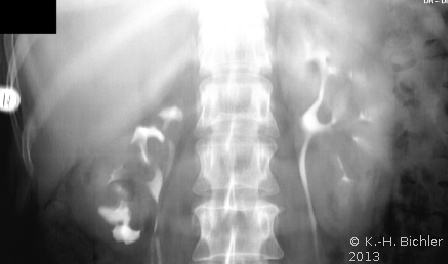

Das Ausscheidungsurogramm bei einer Patientin mit rezidivierenden Harnwegsinfekten mit Dysurie und immer wieder auftretenden Flankenschmerzen rechts gab Verdacht auf eine doppelt angelegte Niere rechts mit kleinem separaten Organ (Abbildung 6).

Das retrograde Pyelogramm rechts bestätigte die Diagnose. Es fanden sich zwei getrennte Ostien und in der retrograden Darstellung zwei Ureteren, wobei die distale Harnleiteröffnung zu der

oberen kleinen Niere gehörte

Weigert-Meyersche RegelDer Ureter des unteren Anteils mündet orthotop, der Ureter des oberen Anteils kreuzt den des unteren und mündet kaudal davon.